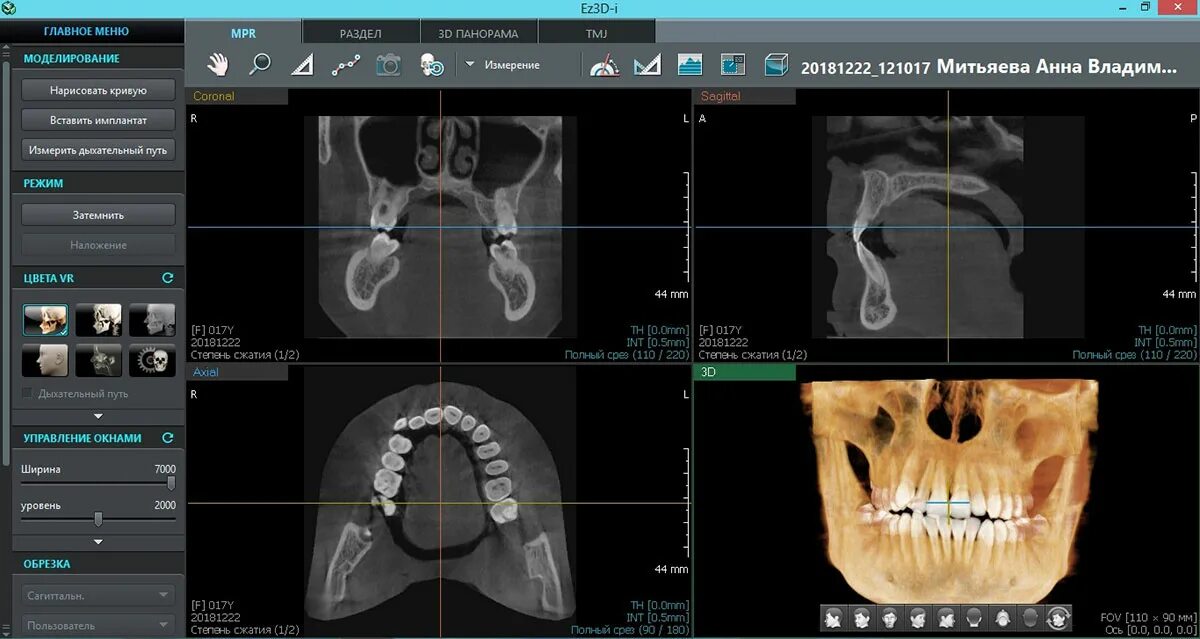

Какой программой открыть кт